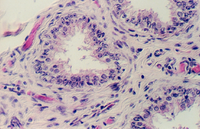

The lumen of this gland is thrown into many folds that appear to branch. This creates a labyrinth of channels, tubes, and pockets into which the secretory product flows. The epithelium shown in the photos below may be simple columnar with patches of pseudostratified epithelium. The appearance of the epithelium is variable and dependent on age and the level of androgen production. One can see some lipochrome pigment in the epithelium, which is present in elderly males. Look at the wall of the gland and again, there are numerous bundles of smooth muscle.

What does the seminal vesicle contribute to the semen?